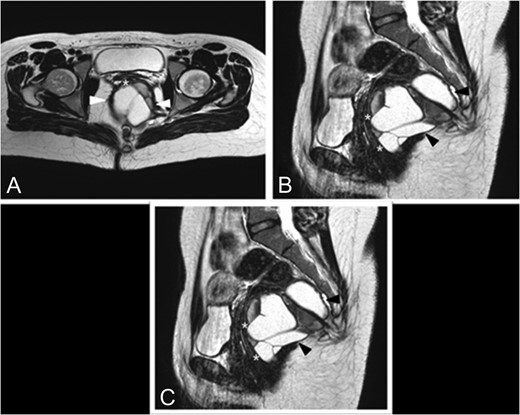

At 8 months follow-up the patient complaint of mild constipation. On digital rectal examination a small (2–3 cm) tender fluctuant extraluminal retrorectal mass was palpable above the anal verge. At MRI the TSE T2-weighted image shows a recurrent cystic lesion expanded in the posterior pararectal space in the context of the levator ani muscle (Fig. 2A–C).

Eight months follow-up MRI. (A) This sagittal TSE T2-weighted image shows a recurrent cystic lesion (+) expanded in the posterior pararectal space, containing serum-proteinaceous material, following the course of the rectal distal portion (*) in the context of the levator ani muscle. (B) Axial TSE T2-weighted images show the cystic lesion (arrowhead) closely adhering to the posterior rectal wall. (C) Coronal TSE T2-weighted images demostrate the relations among the cystic lesion (black*), the rectum (white*) and the levator ani muscle (arrowhead).